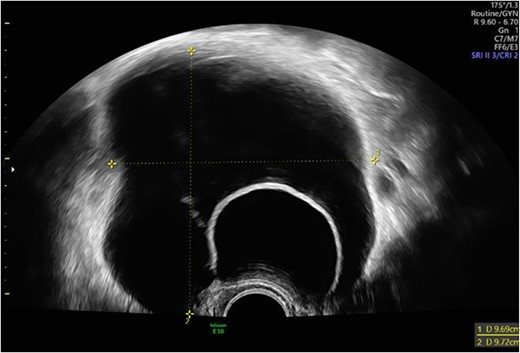

We report of a 29-year-old patient (G2/P1) who was referred in our department with secondary infertility and suspicion of hydrosalpinx for further diagnosis. The patient had no previous diseases, did not take medication regularly and had a regular menstrual cycle. The patient had undergone surgical laparoscopy with salpingotomy on the right side for extrauterine pregnancy. Preoperatively, there was the sonographic suspicion of hydrosalpinx on the left side (64 × 26 mm2, echo-poor with dorsal sound enhancement) and of a simple ovarian cyst of the left ovary (Fig. 1). Otherwise, sonography revealed unremarkable internal genitalia, no free fluid in the Douglas space. Hysteroscopy, chromopertubation, laparoscopy and cyst extirpation on the left and, if necessary, salpingectomy on the left were discussed with the patient.

Preoperative sonographic suspicion of hydrosalpinx on the left side (64 × 26 mm2, echo-poor with dorsal sound enhancement).